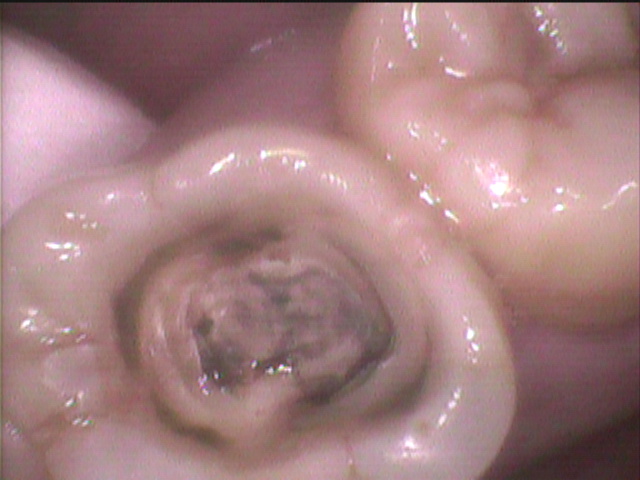

持続的な痛みがあるので、奥側の歯の髄腔を開けました。

歯根からの虫歯が、神経のある髄腔に達していましたので

神経が変性して、痛みが出たと考えられます。

この後、根管処置をして修復してゆきます。